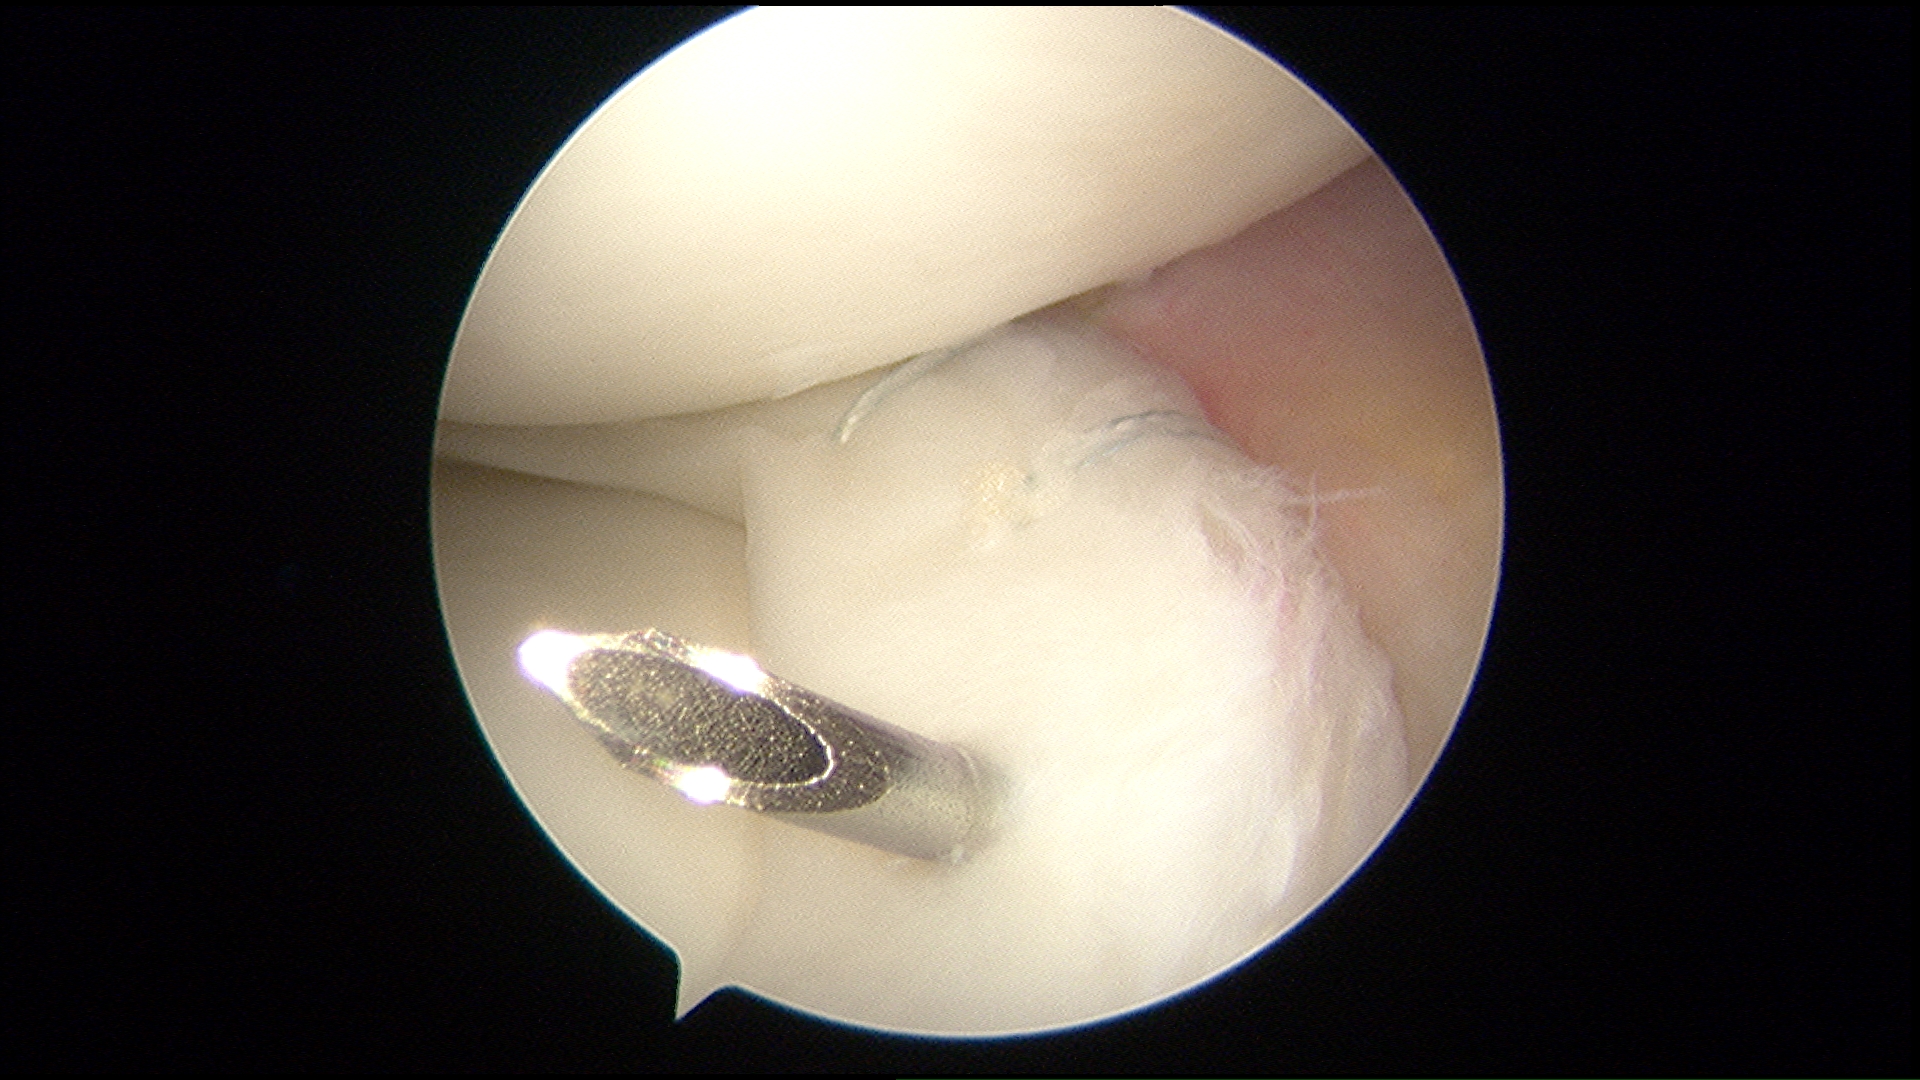

If your symptoms persist with non-surgical treatment, Dr. Ahmad may suggest arthroscopic surgery.

- Knee arthroscopy: One of the most commonly performed surgical procedures, includes inserting a miniature camera into the knee through a small incision. This provides a clear view of the inside of the knee, which Dr. Ahmad uses to insert surgical instruments through to trim or repair your tear.

- Partial meniscectomy. In this procedure, the damaged meniscus tissue is trimmed away.

- Meniscus repair: Some meniscus tears can be repaired by suturing (stitching) the torn pieces together. Whether a tear can be successfully treated with repair depends upon the type of tear, as well as the overall condition of the injured meniscus. Because the meniscus must heal back together, recovery time for a repair is much longer than from a meniscectomy.